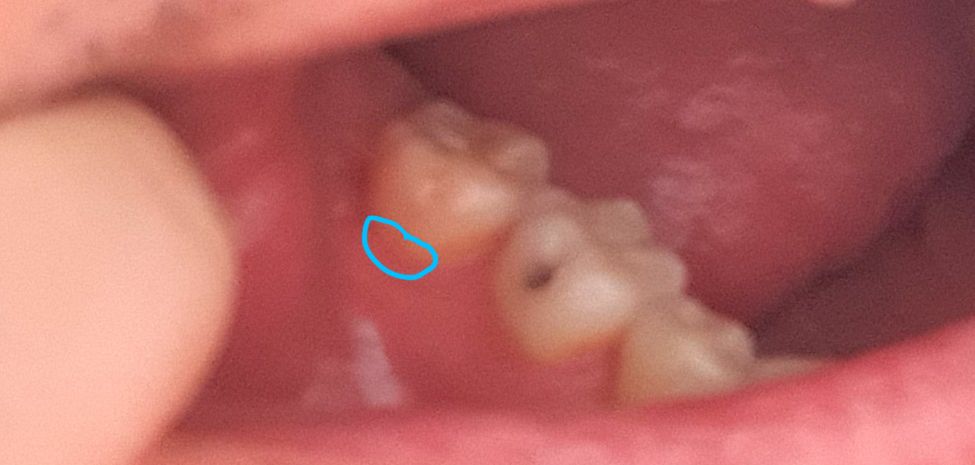

사랑니 발치 후 바로 앞 어금니 잇몸 내려감?

안녕하세요. 작년 5월 매복 사랑니 발치(좌측) 후 문제가 없다가

최근 시려와서 보니, 우측 어금니에 비해 잇몸이 많이 내려왔더라고요.

사진/그림과 같이 앞 어금니 잇몸 부분이 시린데...

• 2번 째 사진